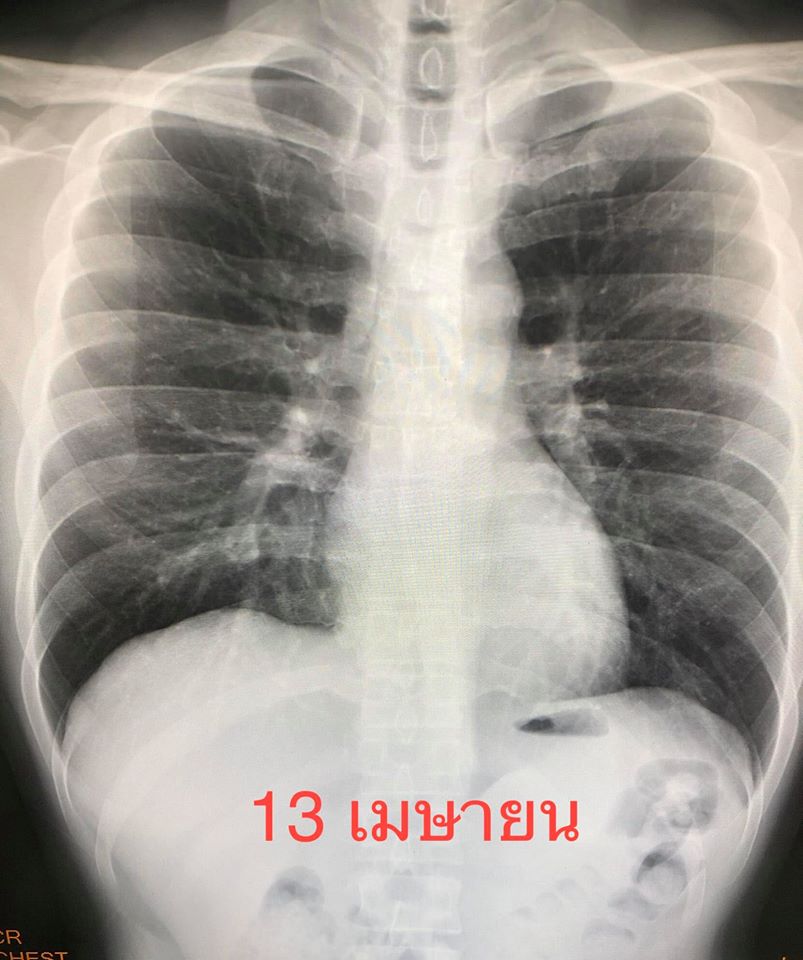

ได้เริ่มยา Lopinavir/ Ritonavir และ ยา Chloroquine ระหว่างอยู่โรงพยาบาล มีไข้สูง 38.5 องศาเซลเซียส เอกซเรย์ปอดวันที่ 17 มี.ค.แย่ลงเห็นฝ้าขาวเพิ่มขึ้นที่ปอดด้านขวากลางและล่าง (ดูรูป)ได้เพิ่มยา Favipiravir อีก 1 ขนาน หลังทานยาฟาวิพิราเวียร์ อาการดีขึ้น ไข้ค่อยๆลง ไม่เหนื่อย ได้ยาทั้งหมด 10 วัน ติดตามเอกซเรย์ปอดวันที่ 13 เมษายน ฝ้าขาวในปอดข้างขวาหายไป กลับมาเป็นปกติ(ดูรูป) ให้กลับบ้านวันที่ 13 เม.ย.รวมเวลาอยู่ในรพ. 30 วัน